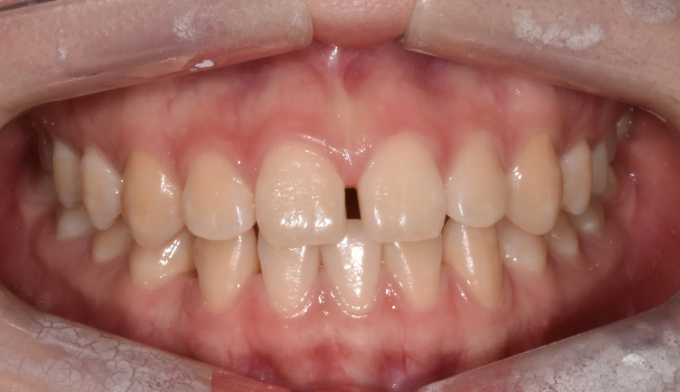

불규칙앞니

40대

2025.02.10